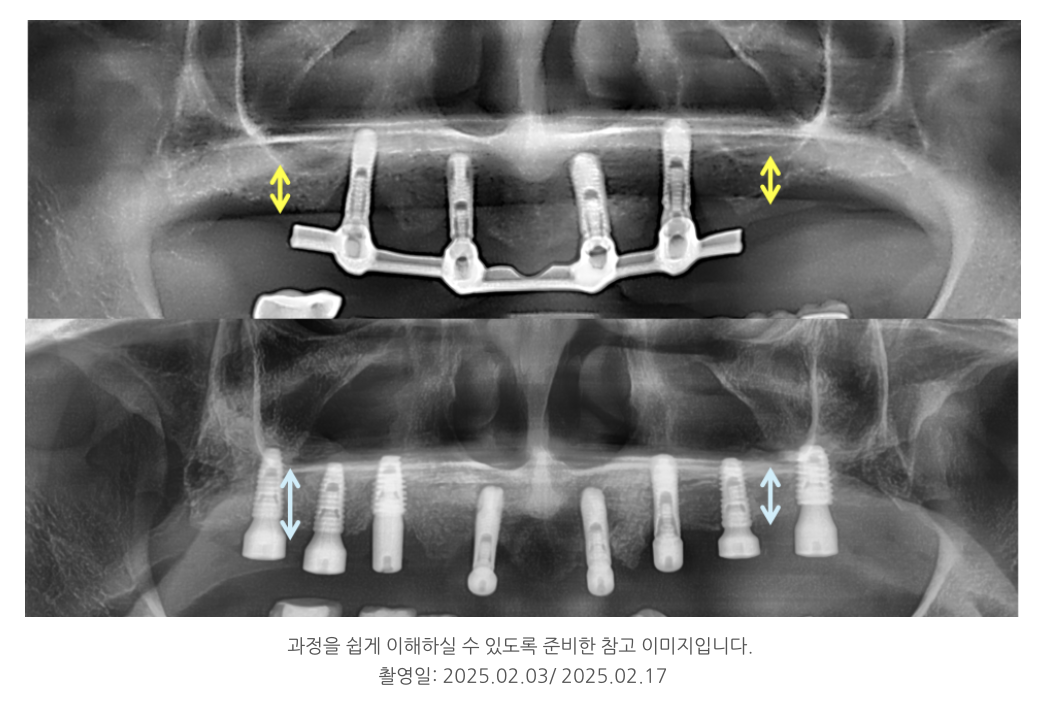

이 환자분 역시 위턱에 임플란트 4개를 심고

bar(바) 형태로 틀니를 걸어 사용하는 구조였는데,

특정 부위에 힘이 과도하게 전달되어 뼈 흡수가 일어났습니다.

기존 임플란트 중 상태가 양호한 2개는 보존하고,

부족한 부위에는 새로 6개를 심어 총 8개로 구성했습니다.

이로써 힘이 고르게 분산되도록 설계했고,

부족한 뼈에는 뼈이식을 병행해 안정성을 높였습니다.